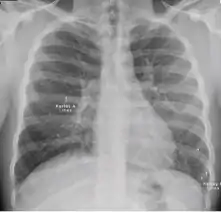

5. Hilar or mediastinal lymphadenopathy (bihilar lymphadenopathy) - Enlargement of lymph nodes in one or both hila or within the mediastinum, with or without associated atelectasis or consolidation.

Chest x-ray showing bilateral hilar adenopathy of primary pulmonary TB